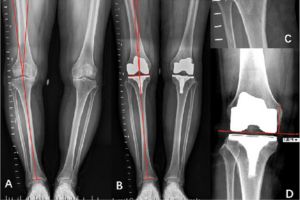

رادیوگرافی الایمنت ویو برای ارزیابی دقیق وضعیت ستون فقرات، زانو و استخوانها در حالت ایستاده